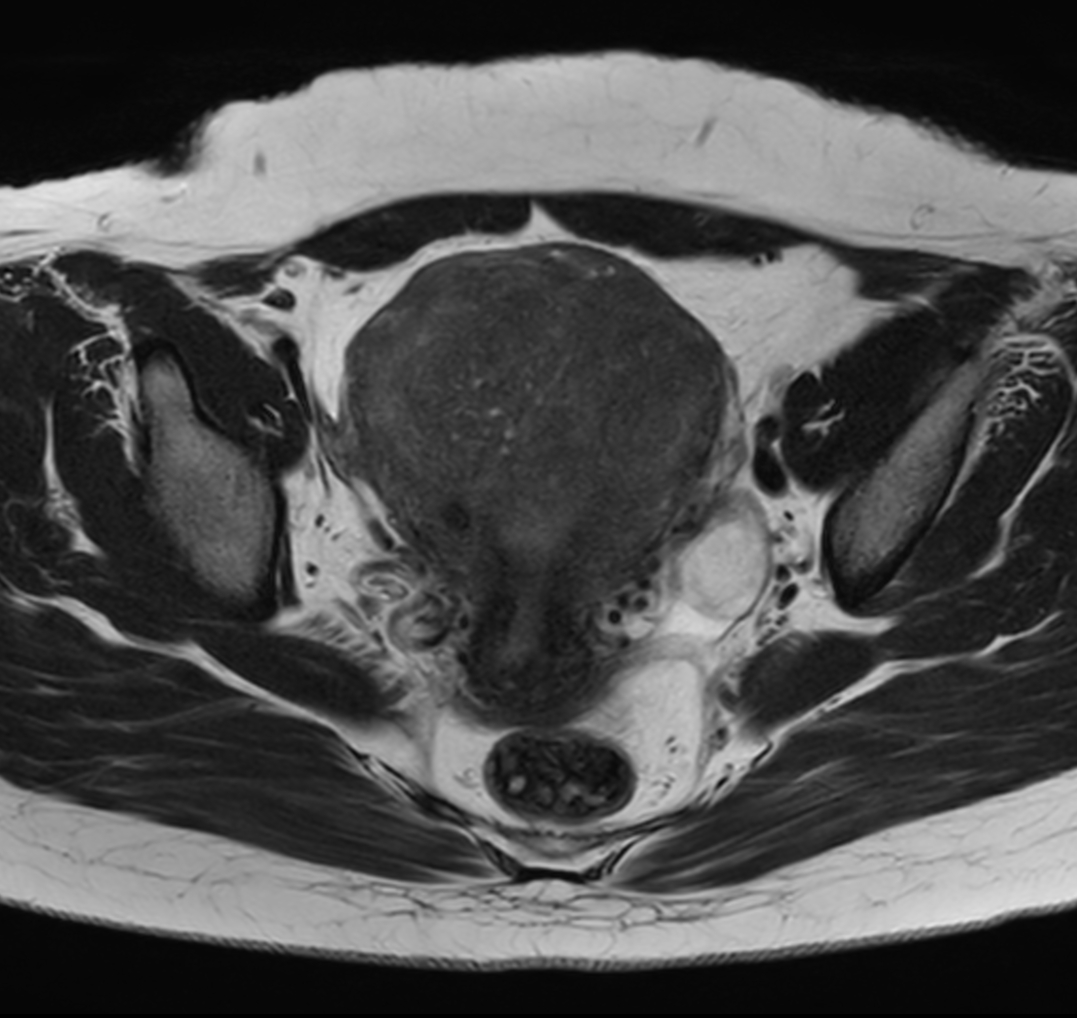

Axial T2w TSE